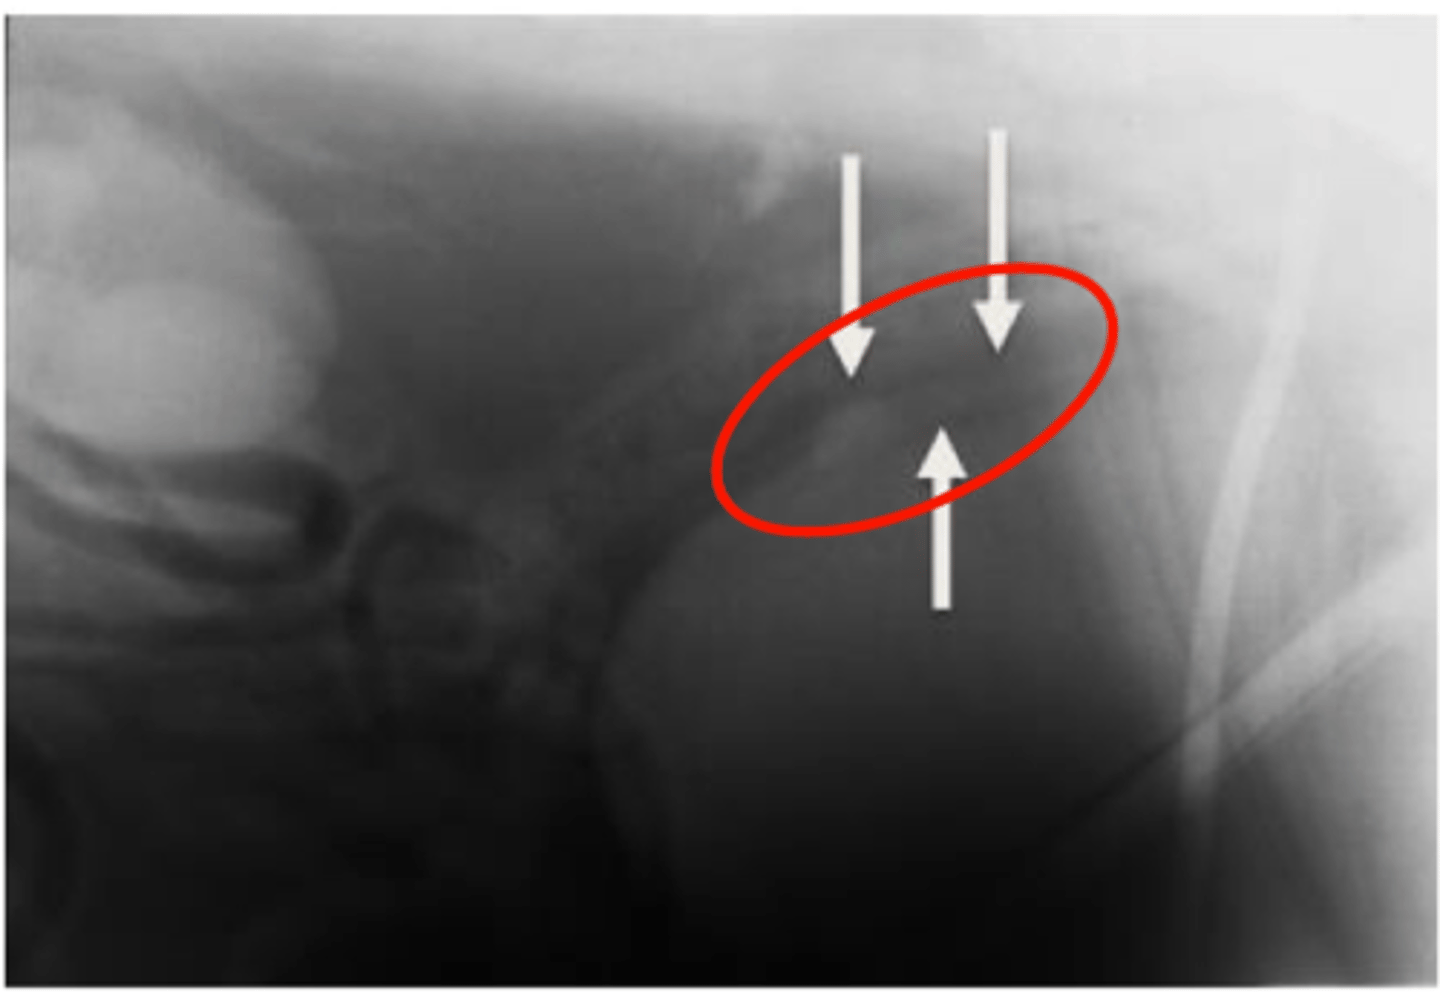

Nephrolithiasis

Presence of renal calculi (stones)

Main radiographic finding is increased opacity

What is a common radiographic abnormality of the urinary bladder diagnosed on radiography?

Calulus/calculi/urolithiasis

Radiopaque: Struvite or calcium oxalate

Non-radiopaque: Urate or cysteine